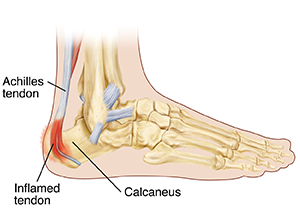

Your child has been diagnosed with Sever disease. This is an irritation of the area where the Achilles tendon attaches to the heel (calcaneus). Constant pulling on the Achilles tendon causes the area to become inflamed. This condition is painful. But with correct care, it can be treated.

Activities that require a lot of running and jumping cause the Achilles tendon to pull on the heel. This can lead to soreness and pain. Sports, such as basketball and soccer, put players at risk of Sever disease.